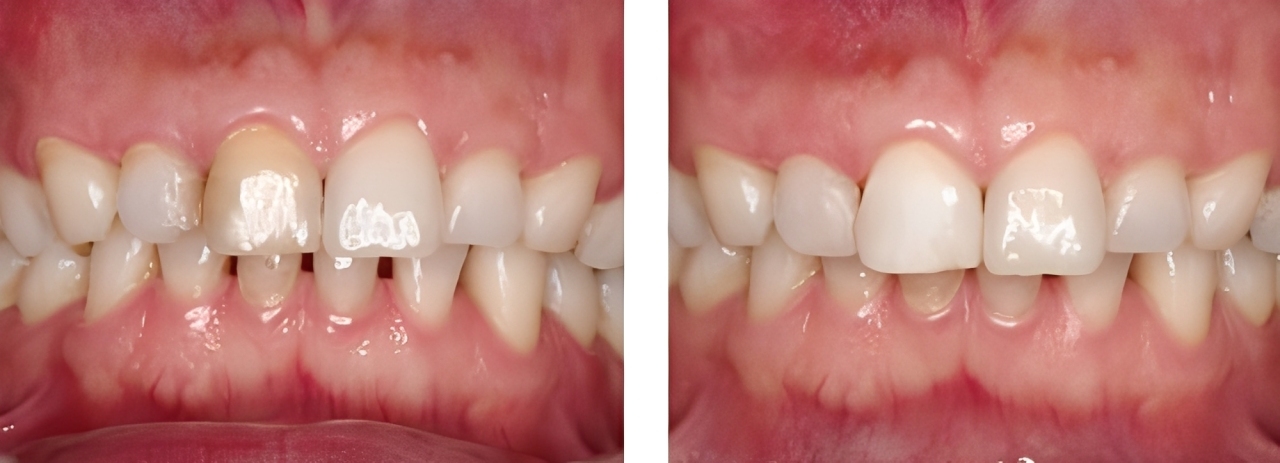

小児歯科

| 治療内容 | 外傷による歯冠破折に対してCRにて破折片の再接着を行った |

|---|---|

| 治療期間・回数 | 1日・1回 |

| 費用 | 保険適用となります |